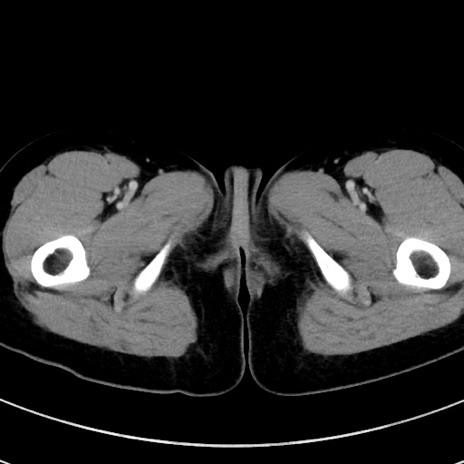

症例17(横断像)

【症例】20歳代女性

【主訴】嘔吐、下腹部痛

【現病歴】昨日夕食後に嘔吐し下腹部痛が出現。本日になっても嘔吐持続し改善しないため来院。

【身体所見】意識清明、BT 37.2℃、BP 108/67mmHg、腹部:平坦、やや硬、下腹部正中から右にかけて圧痛あり、反跳痛軽度あり、tapping pain(+)。

【データ】WBC 13600、CRP 14.94